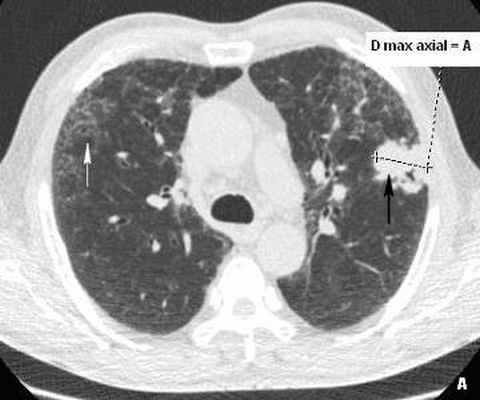

Рис. 3(А, Б). КТ грудной клетки больного Г., 72 лет. Малодифференцированный рак на фоне обычной интерстициальной пневмонии (морфологическая верификация).

А - аксиальный срез на уровне верхних долей легких, выявлены участки диффузного снижения пневматизации по типу «матового стекла», утолщение внутридолькового интерстиция (белая стрелка), в переднем сегменте верхней доли слева на границе интерстициальных изменений и нормальной легочной ткани выявлена субплевральная консолидация неправильной округлой формы (черная стрелка). Б - МПР в коронарной проекции на уровне консолидации. Рассчитанное значение 3 D – коэффициента составило 1.65 ( D max axial / D min cor = А/В = 1.65). Проведена морфологическая верификация консолидации под контролем КТ-скопии – диагностирован малодифференцированный рак.